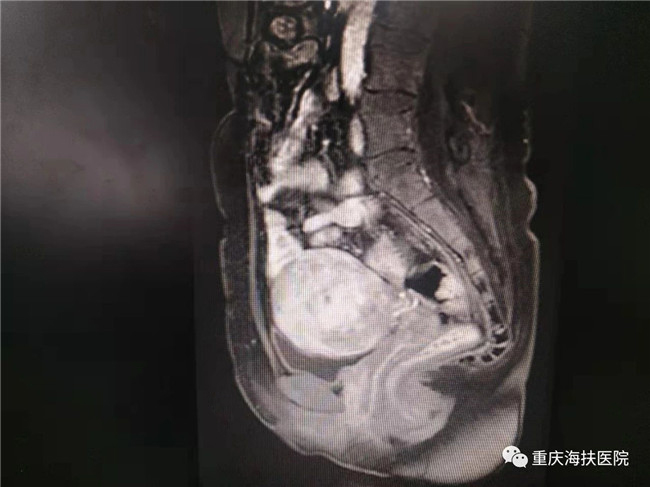

李女士因?yàn)橛斜A糇訉m和再生育的愿望,毅然選擇了不開(kāi)刀、不流血的聚焦超聲消融手術(shù),術(shù)中消融病灶達(dá)6公分,消融效果良好。術(shù)后李女士發(fā)現(xiàn)自己的痛經(jīng)癥狀明顯緩解,并在1年后成功妊娠,于2019年9月18日剖宮產(chǎn)一個(gè)6.2斤的海扶小公主!